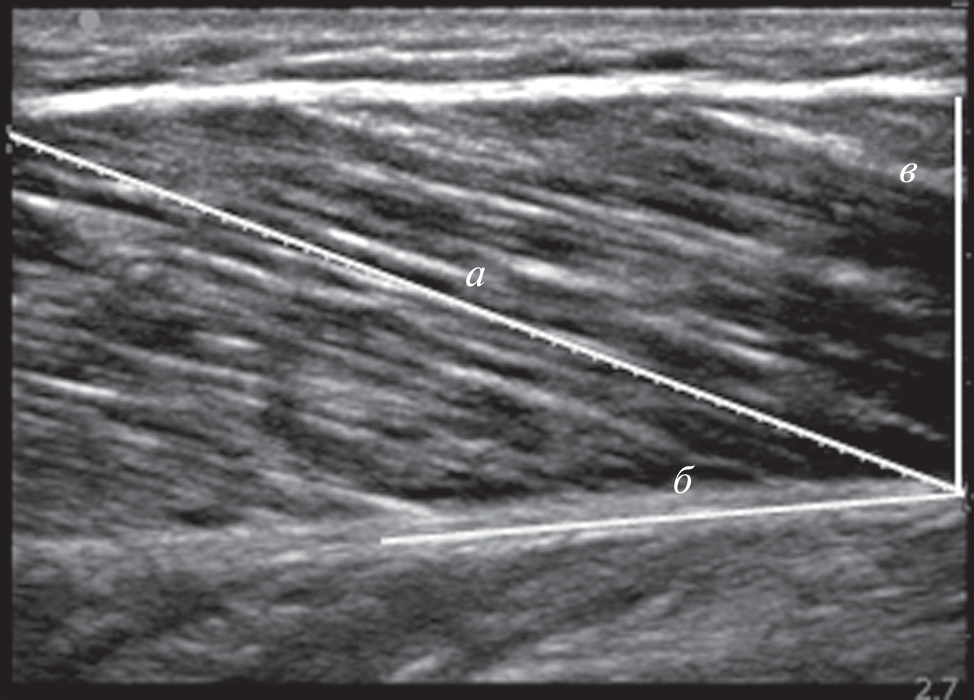

The aim of this study was to first, experimentally measure in vivo changes in the length, fiber angle and thickness of the medial gastrocnemius muscle (MG) in young men in response to changes in foot position and joint moment during isometric plantar flexion and, in secondly, to compare the changes in the above characteristics of the muscular architecture that occur during the transition from a state of rest to a given isometric intensity during plantar flexion. The internal architecture of the MG was determined after 21-day of strict head‑down tilt bed rest (HDT). MG scanning was performed using ultrasound at rest at ankle joint angles of –15° (dorsiflexion), 0° (neutral), +15° and +30° (plantar flexion). Additional ultrasounds were performed during maximal voluntary contraction (MVC) and additionally at 80, 60, 40, and 20% of the MVC with the ankle in neutral position. In each position, longitudinal ultrasound images of the MG were obtained in a relaxed (passive) state with the determination of the length (Lf) and angles of fascicles (Θf) relative to the aponeurosis. After HDT, the thickness of the MG during graduated isometric force up to 80% of the MVC in the neutral position of the ankle joint remained constant. Various Lf and Θf and their changes after HDT can be a limiting factor in the generation of muscle contractile functions. The results of the study show that the change in muscle structure during contraction compared to rest, as measured by changes in muscle architecture, can be used to assess muscle mechanical output.